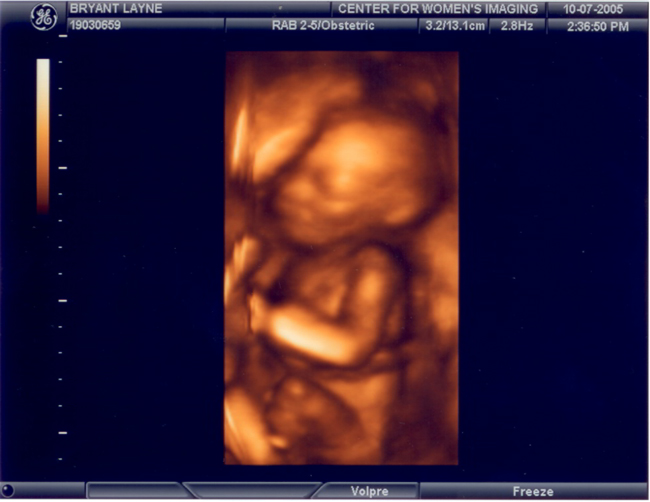

Caroline's Second Ultrasound

These pictures were taken on October 7th at about 20 weeks.